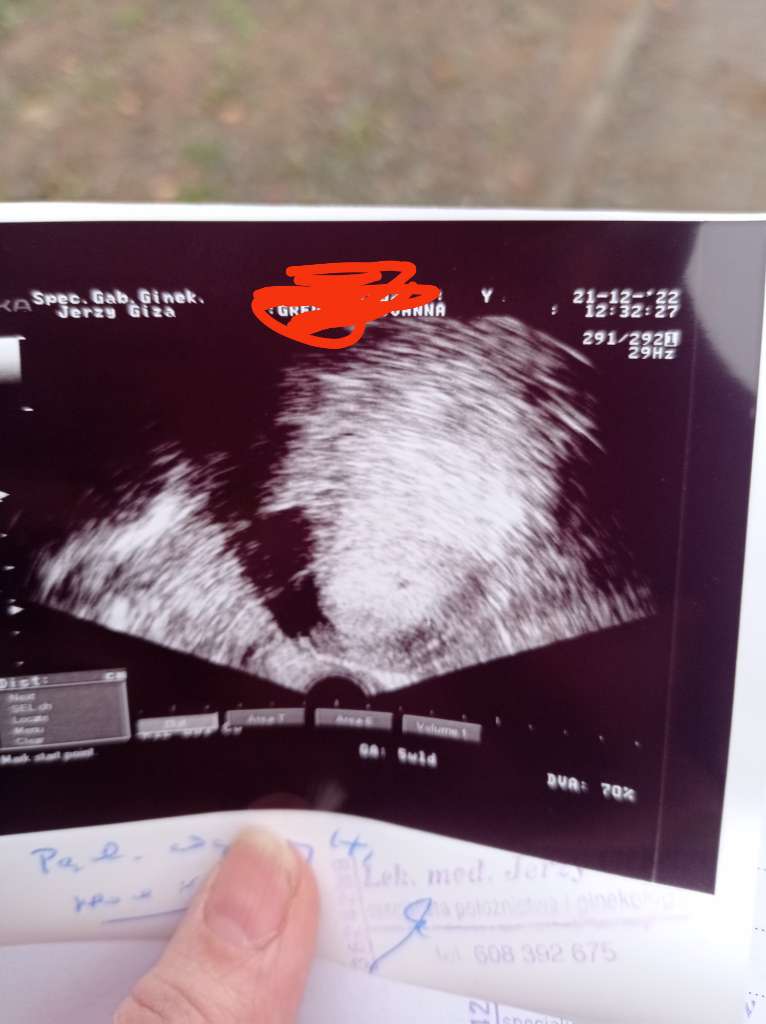

nie robilam juz bety u mnie w ogole jakos dziwnie. Bo poszlam do lekarza pierwszego rosno 5 tygodni po @. Powiedzial ze nuby to 2/3 tydzien ciazy bylo widac pecherzych. Kazal przyjsc za dwa tygodnie i wtedy powiedzial ze to 4/5 tydzien jest cialko zolte nie ma zarodka. Wystraszylam sie na drugi dzien poszlam do kolejnego i powiedzial ze to 5 tydzien i 1 dzien i jest zarodek. I tak kolejno wyszly zdjecia usg od 2 lekarzy.A beta na jakim poziomie? Z ciekawości spytam. Bo do wizyty u lekarza prawie tydzień a nie mogę się doliczyć Bo z bety wychodzi mi że 6 tydz. Z miesiączki że 4/5 mc

Może ma znaczenie dobra aparatura i umiejętnośc szukanianie robilam juz bety u mnie w ogole jakos dziwnie. Bo poszlam do lekarza pierwszego rosno 5 tygodni po @. Powiedzial ze nuby to 2/3 tydzien ciazy bylo widac pecherzych. Kazal przyjsc za dwa tygodnie i wtedy powiedzial ze to 4/5 tydzien jest cialko zolte nie ma zarodka. Wystraszylam sie na drugi dzien poszlam do kolejnego i powiedzial ze to 5 tydzien i 1 dzien i jest zarodek. I tak kolejno wyszly zdjecia usg od 2 lekarzy.